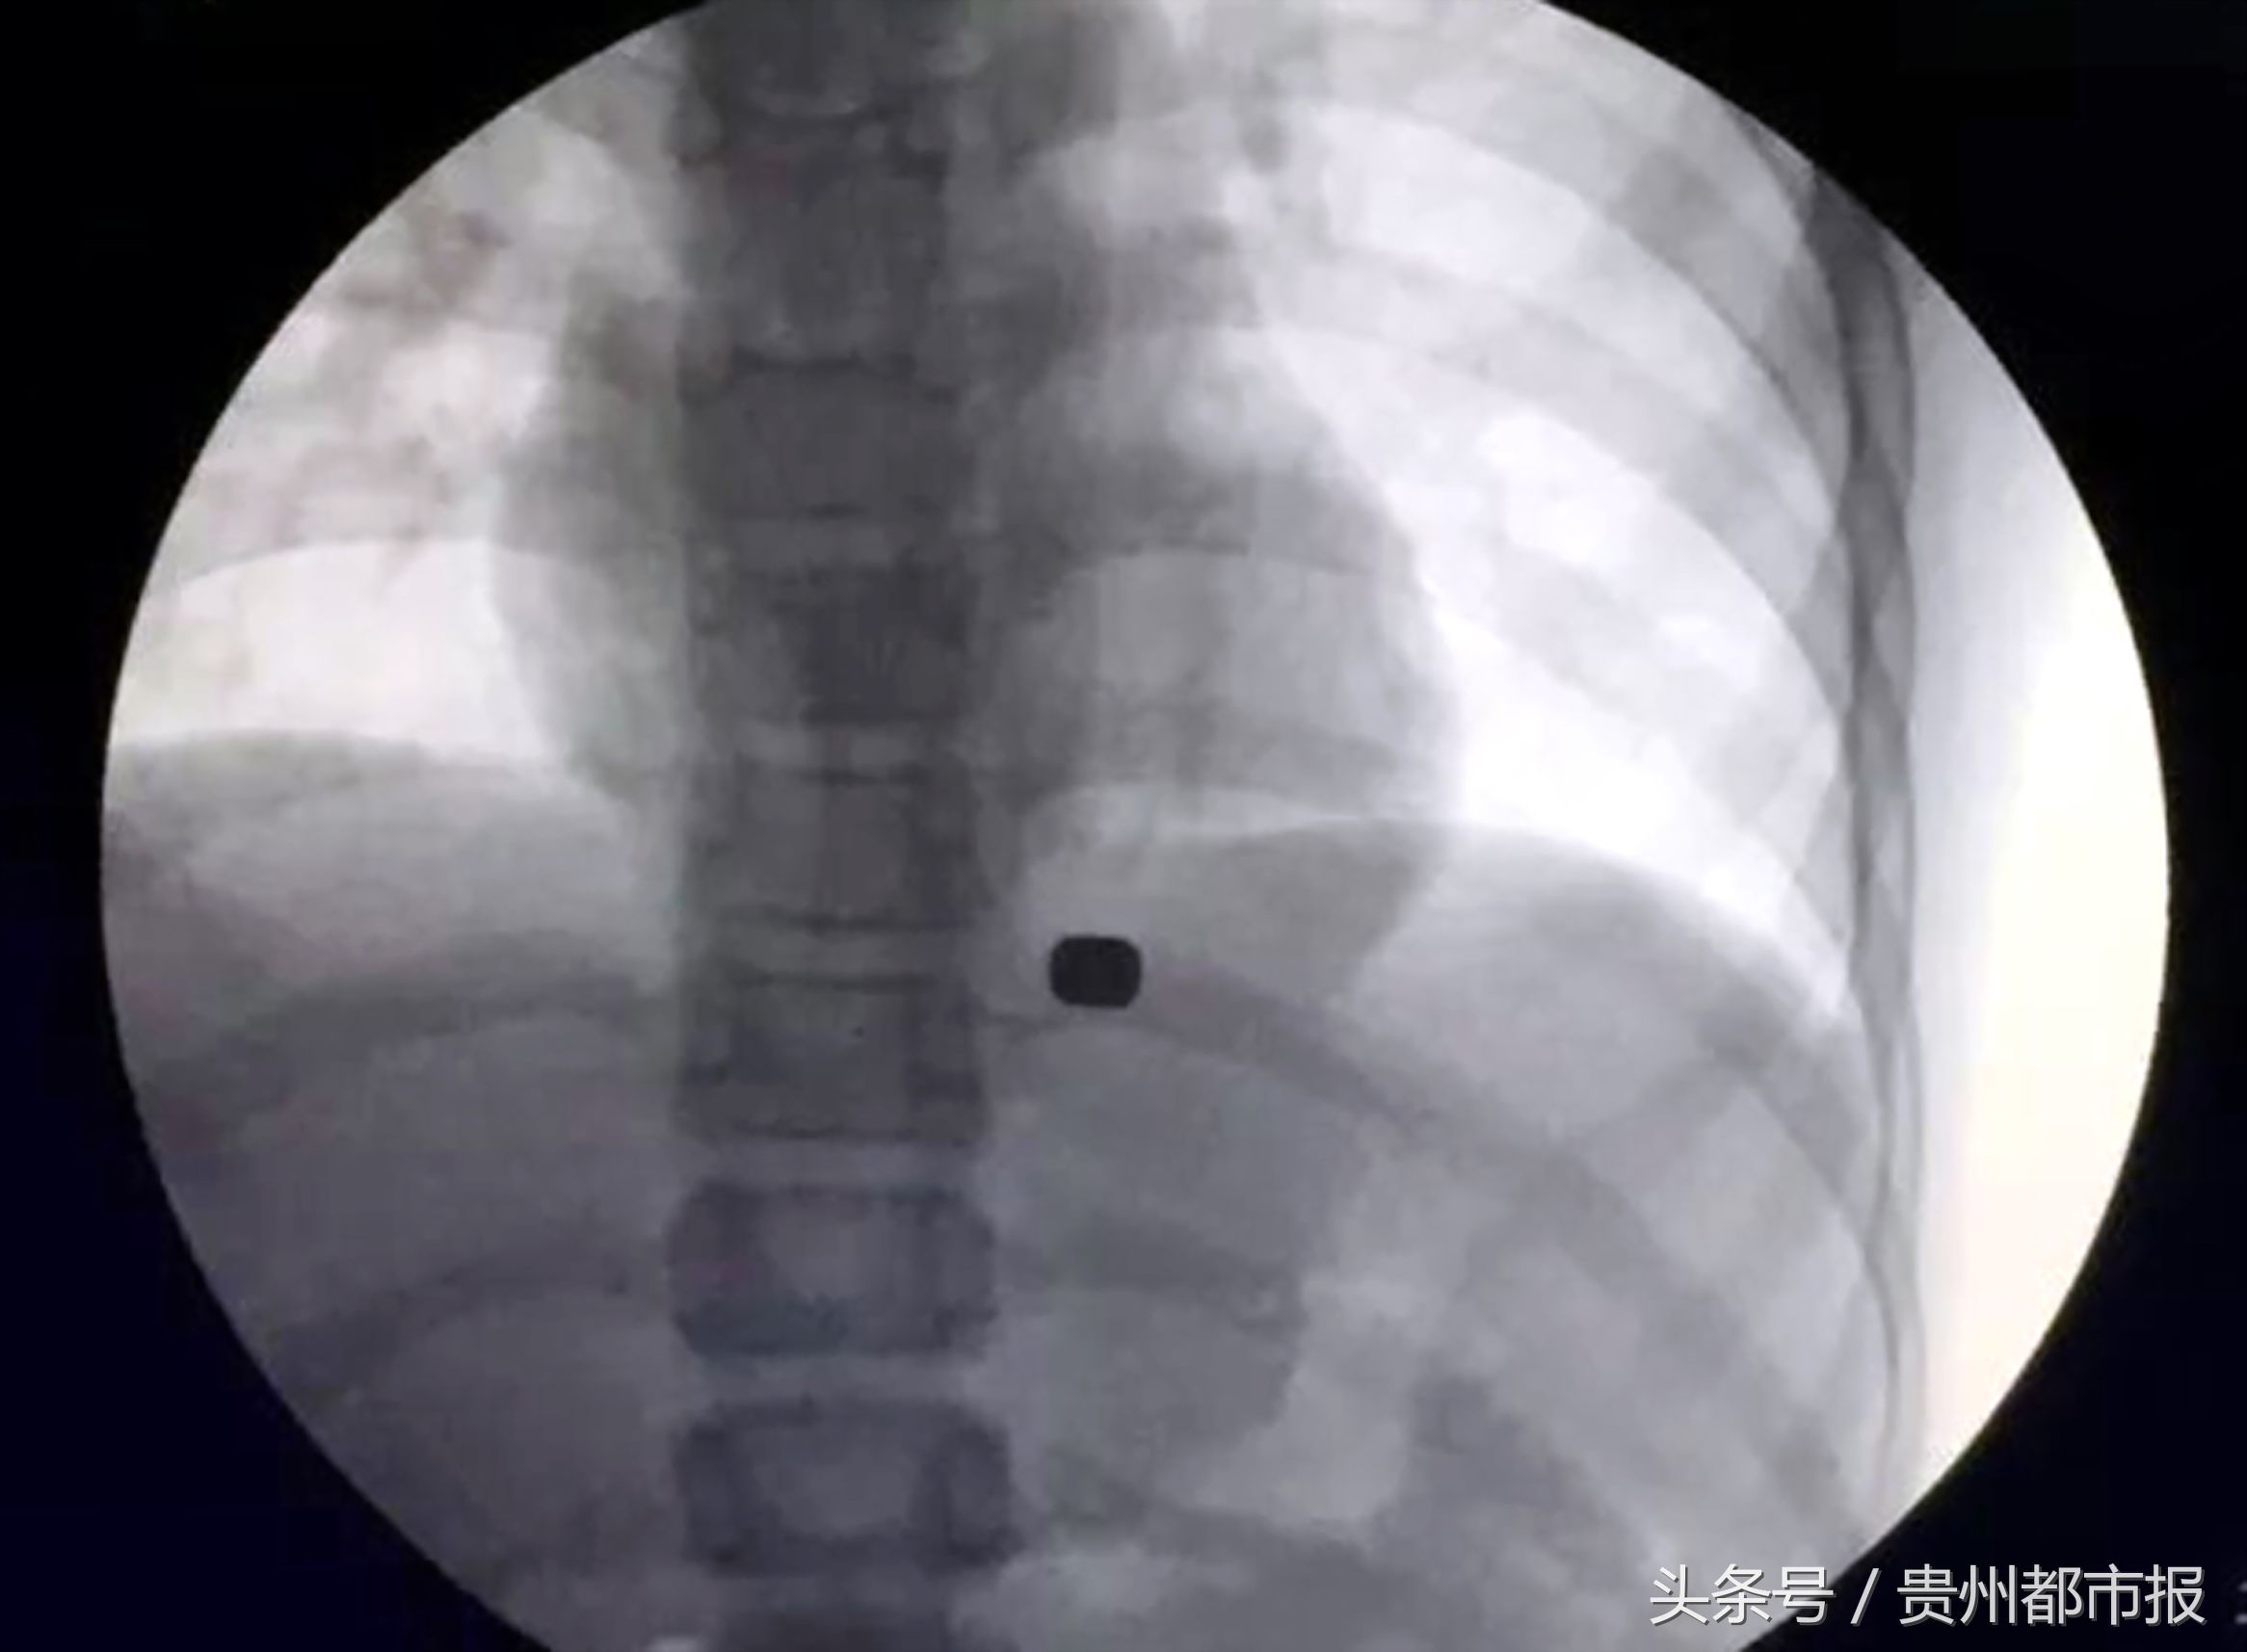

小军在川大华西医院照片发现磁铁在体内。

11月6日,父母带着小军来到四川大学华西医院门诊。消化内镜中心主任胡兵教授,了解到小军误吞磁铁的过程。“磁铁磁力大,加之周边组织贴得很紧,消化内镜的夹子根本夹不住;即便是开胸手术,也可能找不到两块磁铁,甚至娃娃会有大出血的危险。”看着小军,胡兵教授也是一筹莫展,他思考着怎样通过一种损伤最小的方式,将小军体内的磁铁取出。